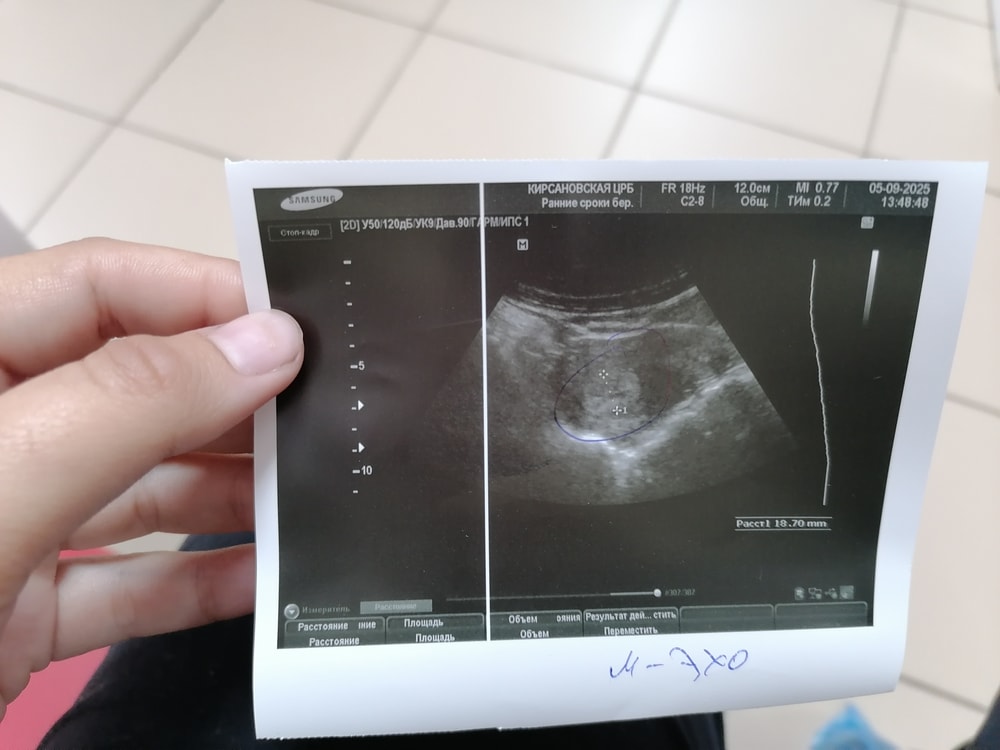

Ольга Сергеева, это на шейку похоже, и диаметр как будто замеряли, судя по пунктиру Беременности не видно ХГЧ какой?

Нет, у вас не подтверждена беременность даже малого срока. Вы либо слишком рано пришли на узи, либо вы не беременны. Желтое тело тоже под вопросом почему-то, хотя прогрессирующее ЖТ узист увидит всегда, у него определенная структура с кровеносными сосудами. У вас же жидкостная структура как обычная киста желтого тела, которая к месячным уменьшается и уходит полностью. А вы для чего ходили на узи , делали предварительно тест или сдавали хгч (кровь) и они были положительными ?

Ольга Сергеева, здесь нет ничего про плодное яйцо, только активный эндометрий

Ольга Сергеева, пя не нашли. Но вообще толщина эндометрия намекает на возможную беременность

Желтое тело говорит о том что просто была овуляция, ждите , может и быть беременность , может и нет

По узи беременности нет